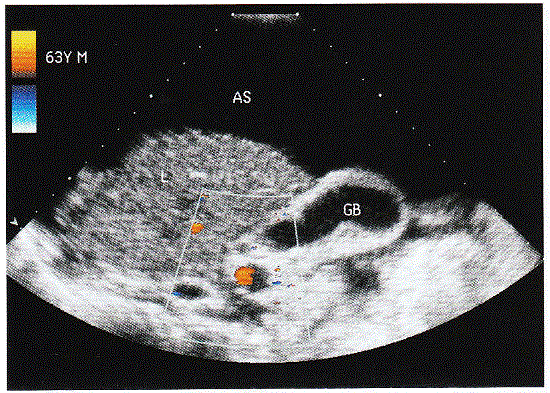

问题 临床资料:男,64岁,自述右上腹不适,持续性隐痛;乙型肝炎病史20年,胃镜发现食道静脉曲张。 超声综合描述:肝形态失常,体积明显缩小,表面凹凸不平,呈锯齿状,内回声粗糙、增强,明显不均匀,呈结节状,部分结节融合,肝中裂增宽,三支肝静脉变细,门静脉内径1.6cm。胆囊大小正常,壁厚0.6cm,呈双边,囊内透声清亮,未见结石及占位。见下列彩图。 超声提示:

选项 A.肝硬化 B.腹水 C.肝病性胆囊 D.以上各项均是

答案 D